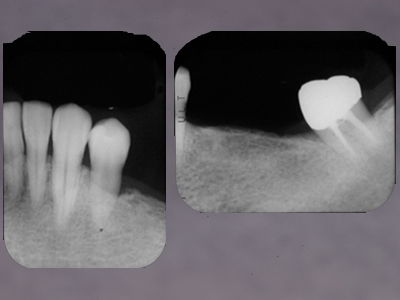

浮腫性の歯肉、全顎にわたりpd8〜10mm、著しい動揺がみられる重症例です。

(下顎前歯部歯肉に注目ください)

初診から7wブラッシング指導のみ。歯肉に変化はみられますが、あえてまだスケーリングはせずもう少し歯肉が変化するのを待ちます。

さらにその3w後。浮腫性の歯肉が乾いた感じに変化しました。歯肉が治ろうとするサインです!この時を見逃さず、ポケット底から縁上まで1歯につき1回でルートプレーニングをします。

1ヶ月後、プロービングデプスは2〜3mmに改善しました。

メインテナンス3年が経過しました。再発もみられず安定しています。